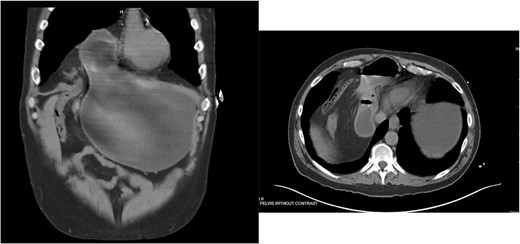

He was admitted for nasogastric decompression and underwent an upper endoscopy with benign findings. Once stable, he was discharged and optimized as an outpatient by adhering to a high-protein liquid diet. He underwent a scheduled robotic-assisted transabdominal preperitoneal (r-TAPP) repair of a type 4 anterior diaphragmatic hernia with mesh. The robot was docked and targeted with four 8 mm robotic ports across the mid-abdomen. A moderately sized hernia containing a loop of the transverse colon was identified. This was gently reduced (Fig. 3).

The falciform ligament was taken down with bipolar cautery. A peritoneal flap was created commencing about 4 cm inferior to the defect. A preperitoneal dissection was then performed to create the flap and to reduce the sac out of the mediastinum (Fig. 4).

Care was taken to avoid injury to the pleura and the pericardium. Once the sac was reduced, the defect’s size was measured as 9 cm in horizontal length by 4 cm in vertical dimension. Primary closure of the defect was performed with a running 0 V-loc absorbable 180 suture.